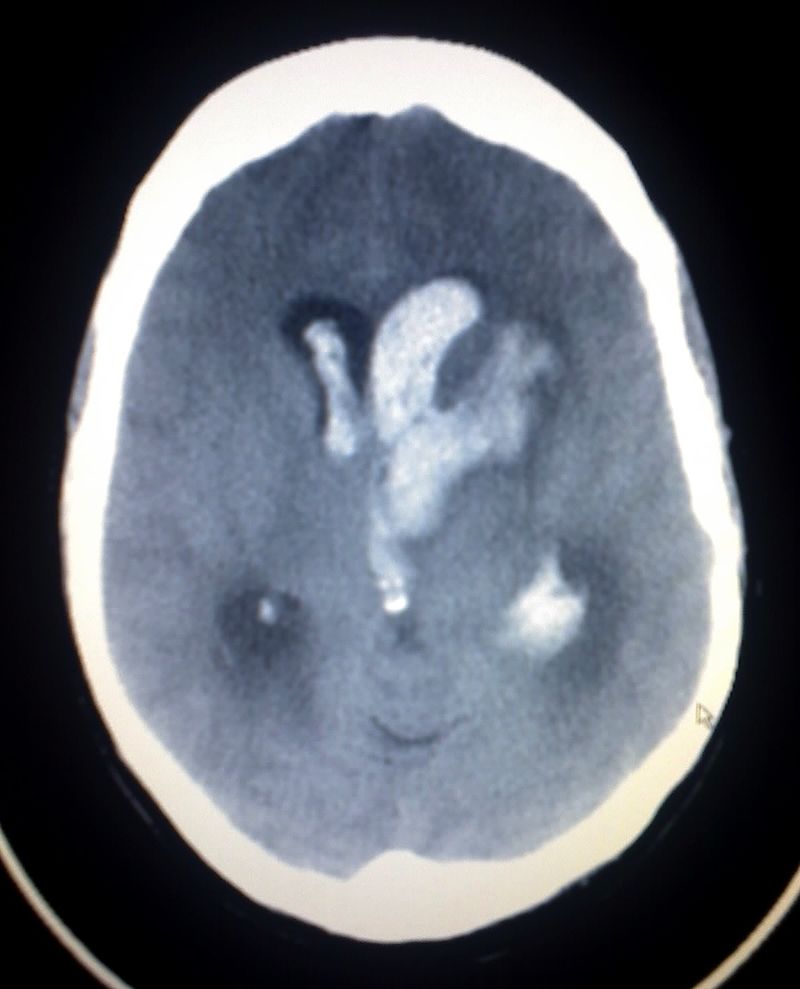

Intracerebral Hemorrhage

An intracerebral hemorrhage is due to brain parenchyma bleeding.

Intracerebral hemorrhage may result from:

- Lenticulostriate vessel rupture

- Aneurysm rupture

The most typical location of the brain involved by intracerebral hemorrhage is the basal ganglia.

Intracerebral hemorrhage hemorrhages may be caused by hypertension.

Subarachnoid Hemorrhage

Subarachnoid hemorrhage is hemorrhage that involves the subarachnoid area of the brain.